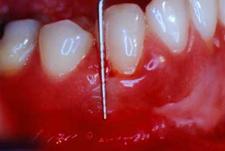

PrefGel este un gel conditionant cu pH neutru (EDTA 24% în gel de carboximetil celuloza) care îndeparteaza "smear layer"-ul restant pe suprafata radiculara dupa îndepartarea mecanica a tesutului de granulatie, placii bacteriene si a tartrului dentar, eliminarea acestui "smear layer" asigurând interactiunea si precipitarea EMD pe suprafata radiculara curata. Aceasta interactiune este vitala pentru regenerarea parodontala care include formarea de cement, ligamente parodontale cu fibre de colagen orientate functional si de os alveolar.

Utilizarea PrefGel asigura îndepartarea "smear layer"-ului si expunerea matricei colagenice a dentinei si cementului prin demineralizare selectiva si fara a afecta vitalitatea tesuturilor parodontale înconjuratoare.

Agentii demineralizanti care actioneaza la pH acid (acid citric, acid fosforic) îndeparteaza si ei "smear layer"-ul dar exista riscul ca acestia sa provoace necroza tesuturilor parodontale înconjuratoare si sa denatureze matricea colagenica.